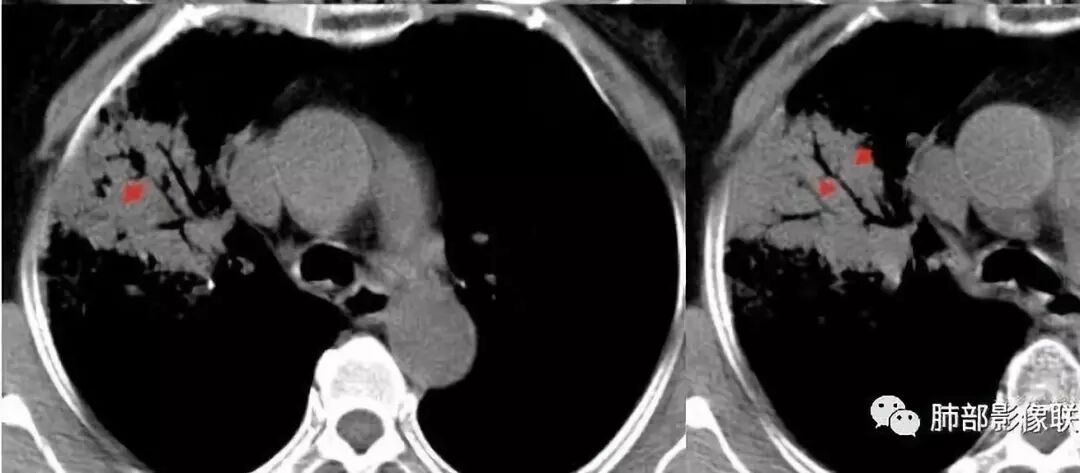

患者老年女性;反复咳嗽咳白粘痰1月,活动后胸闷。

胸CT:右肺上叶实变内可见支气管充气征,近端支气管狭窄,远端扩张,周围可见毛玻璃影,右肺中叶支气管闭塞,并可见气道壁钙化,右肺中叶体积缩小,实变内可见空洞,并可见气液平面,空洞周围可见毛玻璃样影,右肺下叶支气管开口狭窄,右肺门淋巴结肿大。纵隔窗可见病灶与壁层胸膜间隙增宽,考虑良性病变-----感染性病变------TB?

右肺上叶病变,内见钙化及空洞,支气管可见,考虑结核伴出血。

老年女性,慢性病程,咳嗽伴白色粘液痰,无发热腹痛,糖尿病,白细胞及C反应蛋白不高,血沉快,铁蛋白高。胸部CT,右肺上叶大片状实变伴磨玻璃密度影,边界不清,边缘局部膨隆,叶裂弧形下坠,实变影宽基底与胸膜相贴;右肺下叶前基底段见类似病灶;右肺中叶不张并空洞形成,空洞内见气液平面;综合考虑右肺上叶及下叶肺炎型肺癌,右肺中叶结核。

这里是中叶的不张和空洞,有钙化,结核确实也不能排除